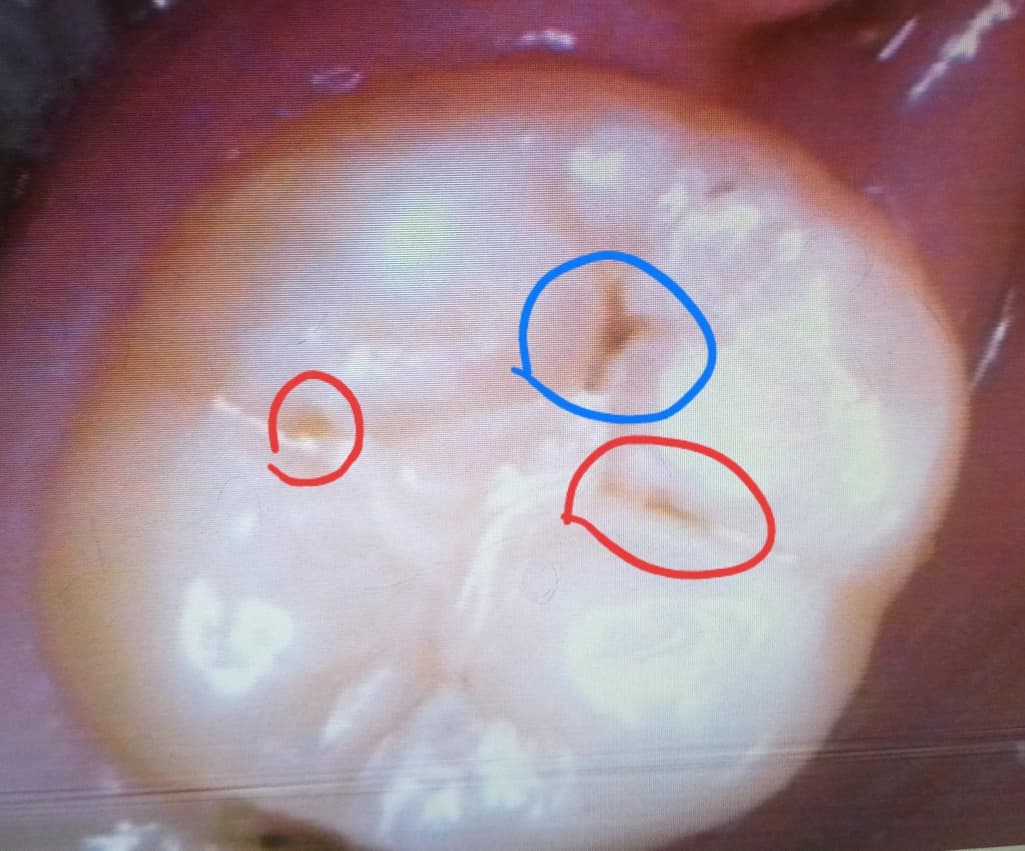

파란색 부분은 처음부터 레진하지 않은 곳이고

뻘간 동그라미 부분이 레진하고 벗겨진 부분이에요.

*의사쌤 답변 : 빨간 동그라마,파란 동그라미 부분 정지우식,C1임 그러니 괜찮다. 그리고 저기 다 할려면 인레인해야 할수있다.